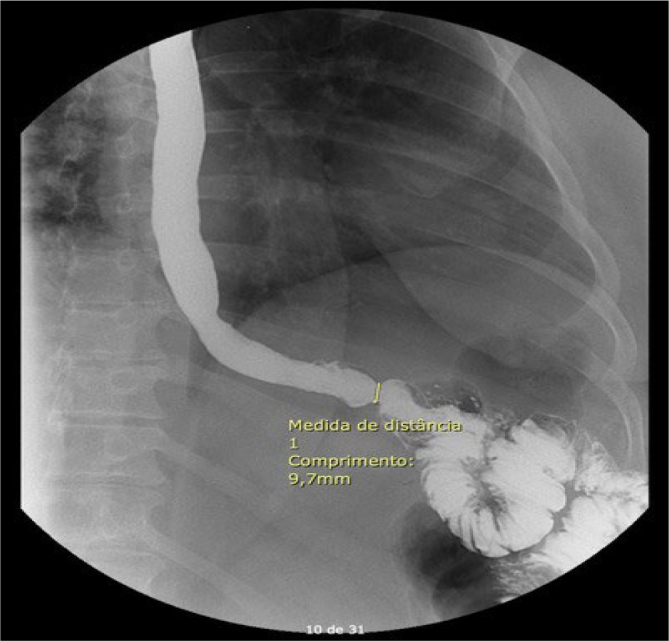

Methods: Manometric evaluation was performed on candidates for bariatric surgery from 2022 to 2024. The examination was conducted according to the protocol of the fourth version of the Chicago Classification, including different positions and provocative maneuvers to confirm the diagnosis of dysmotility. Patients were followed for 90 days after surgery to verify the occurrence of dysphagia or difficulty adapting to the diet.

Results: High-resolution manometry was performed on 46 candidates for bariatric surgery with a mean body mass index of 46.5 kg/m2. Esophagogastric junction outflow obstruction was diagnosed in 16 (34.8%) patients, and ineffective esophageal motility was diagnosed in 8 (17.4%) patients. None of the subjects reported symptoms during the preoperative period. Out of the 46 individuals initially included, 44 underwent bariatric surgery, 23 (52.3%) underwent Roux-en-Y gastric bypass, and 21 (47.7%) underwent sleeve gastrectomy. One patient with esophagogastric junction outflow obstruction reported dysphagia after Roux-en-Y bypass, but symptoms spontaneously resolved during the 90-day follow-up period.